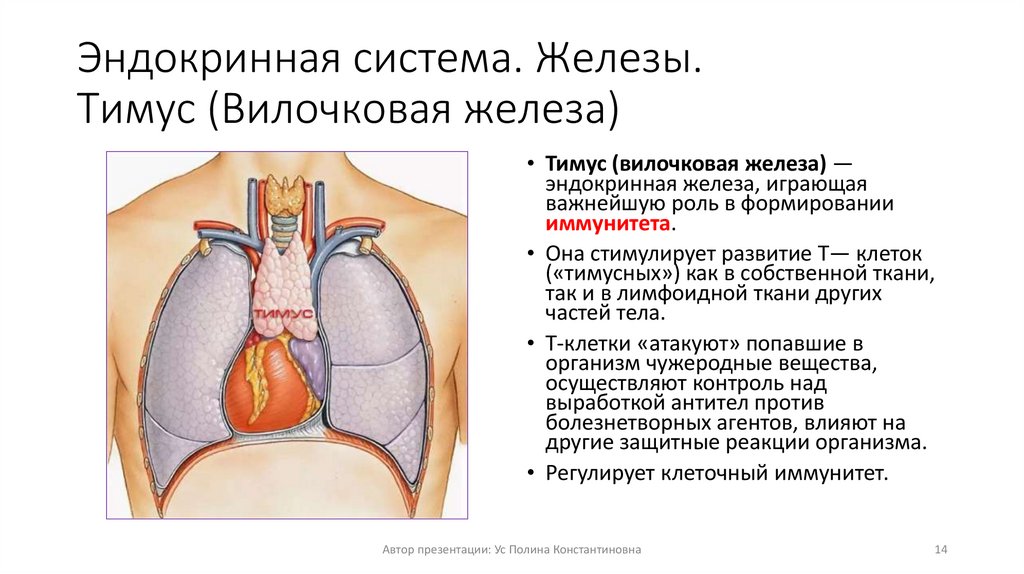

Фотографии вилочковой железы тимуса: структура и функции